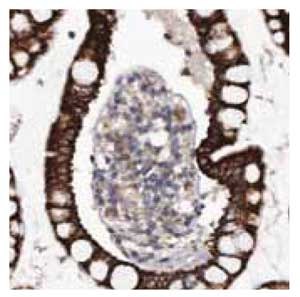

Anti-MGLL.Product No. HPA011994: Immunohistochemical staining of human small intestine shows strong cytoplasmic positivity in glandular cells.